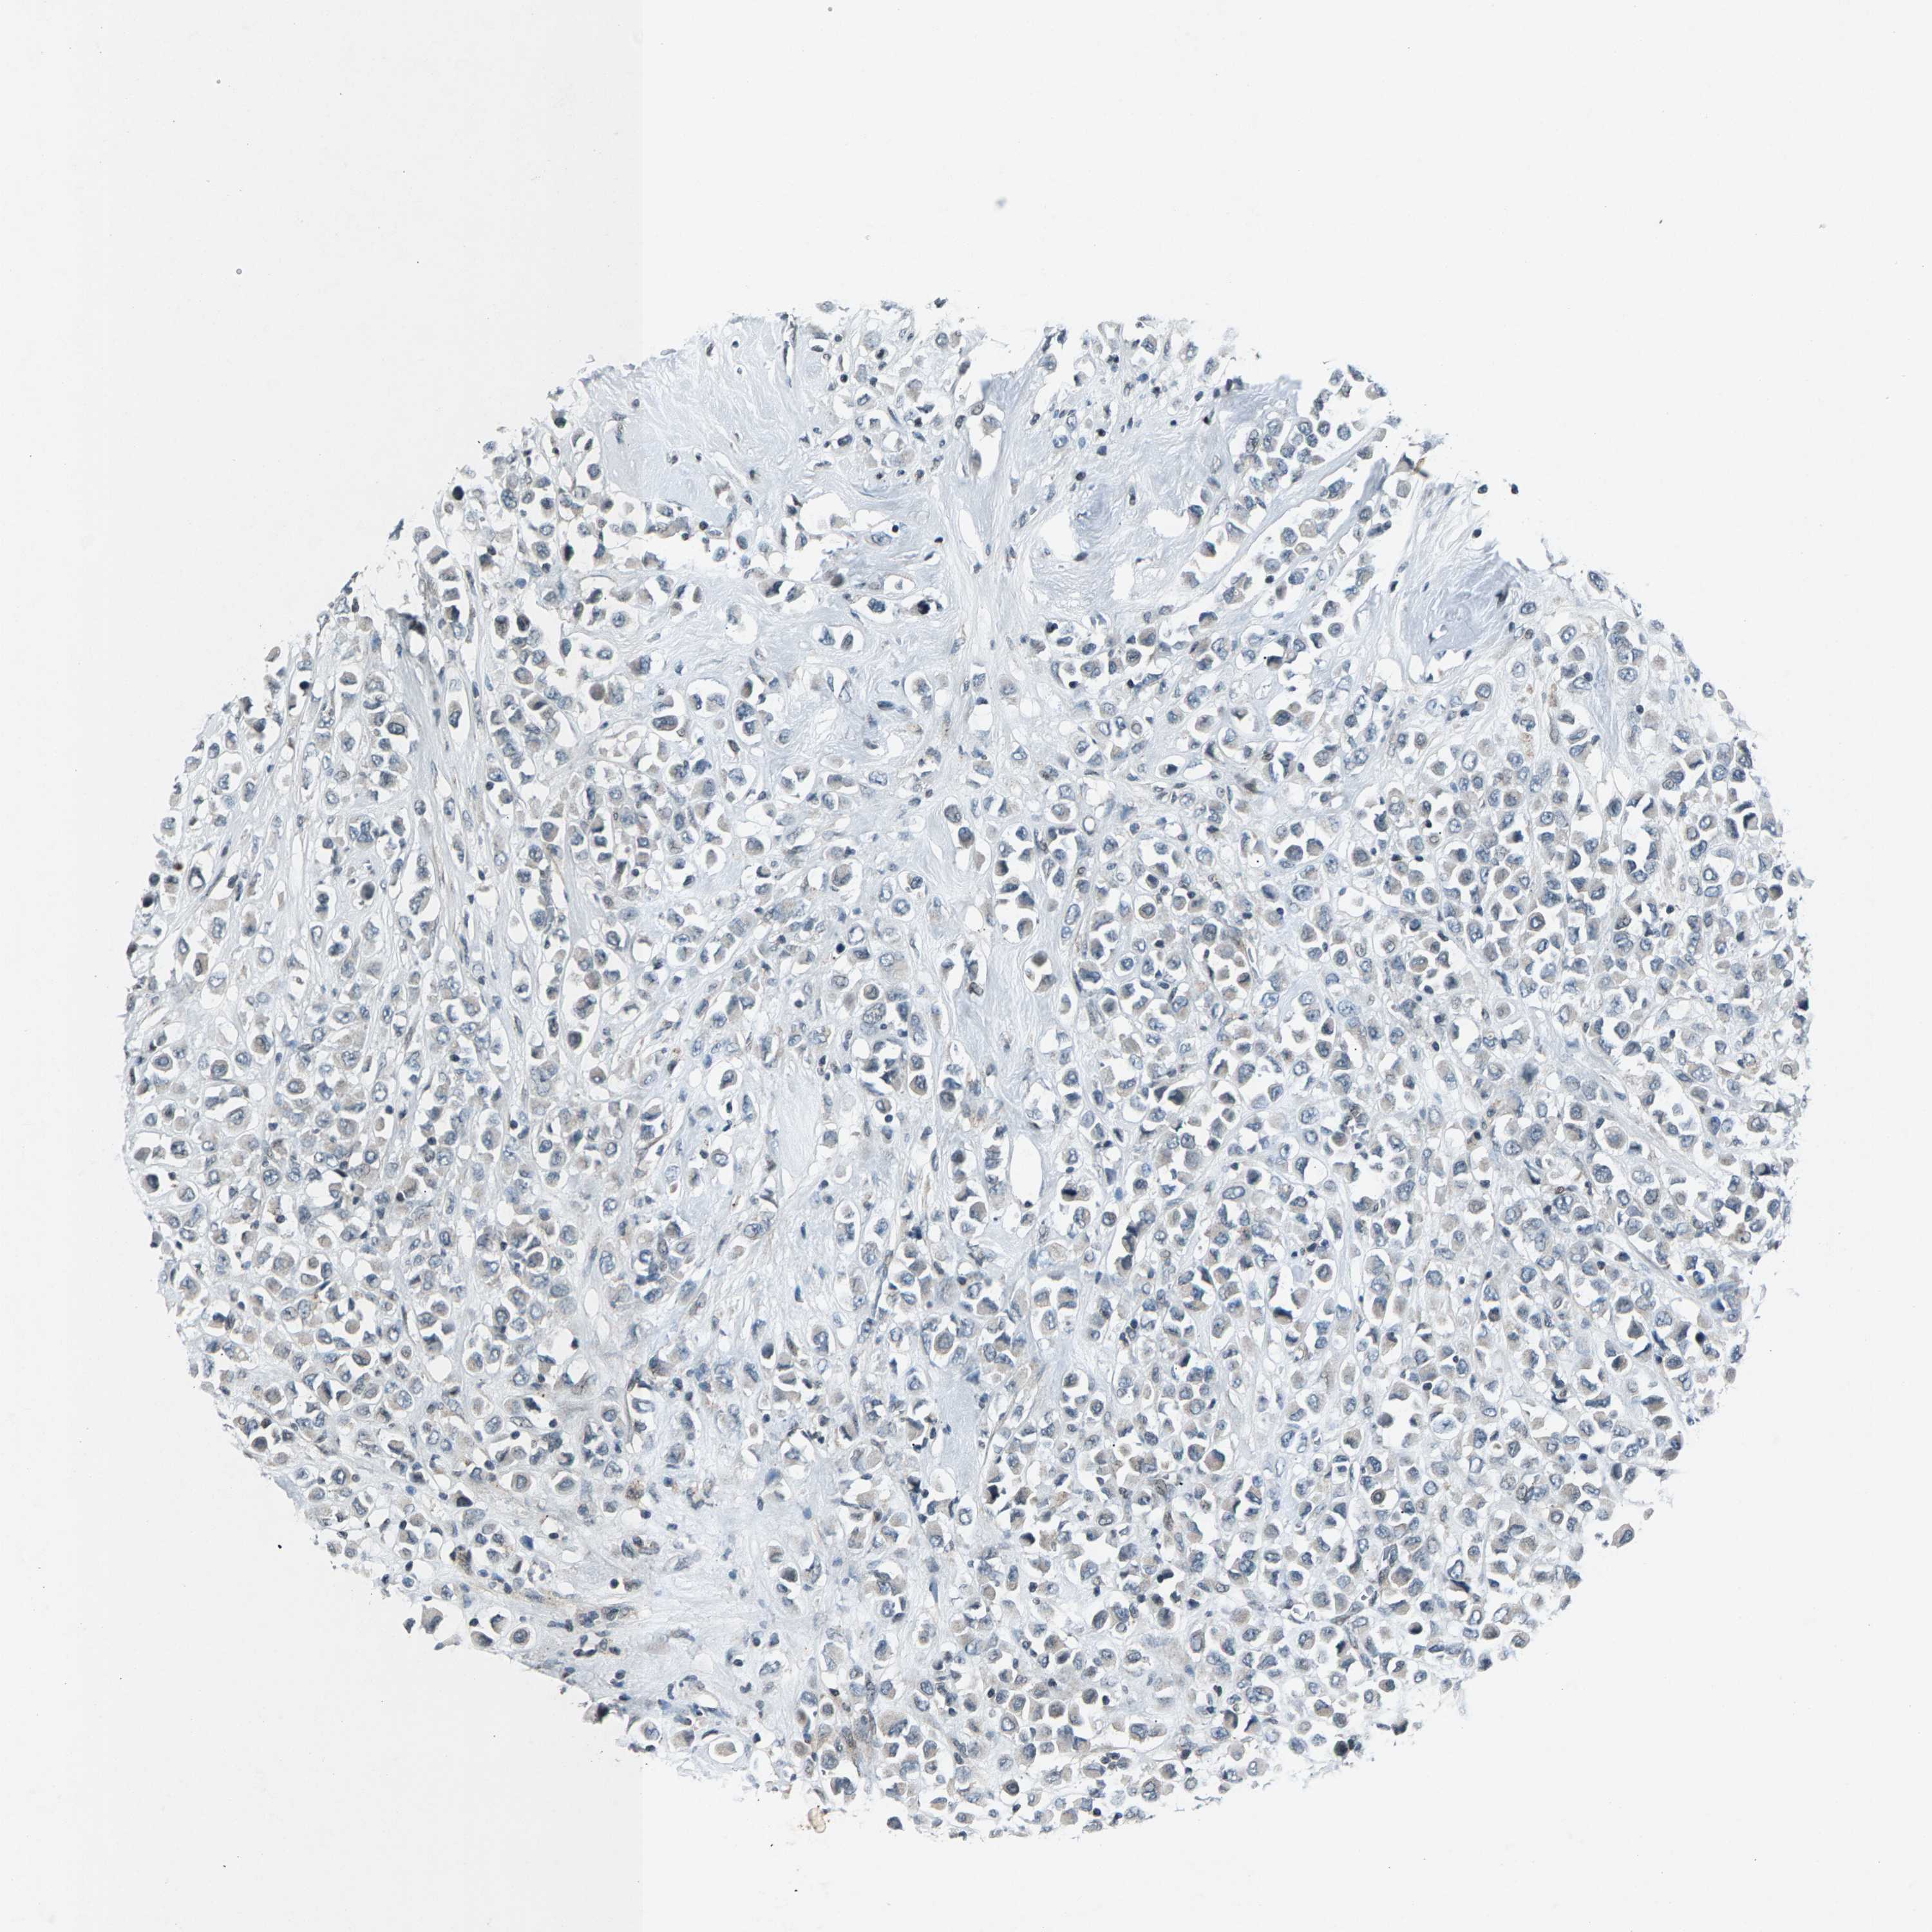

CANCER BREAST CANCER Show tissue menu

Breast cancer

Human cancer

ZPR1 is not prognostic in Breast Invasive Carcinoma (TCGA)